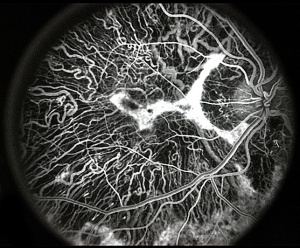

Fluorescein angiography

On fluorescein angiography, scalloped areas of missing choriocapillaris appear hypofluorescent next to brightly hyperfluorescent areas of perfused choriocapillaris (See image below). Although not a common feature, choroidal neovascularization secondary to choroideremia can develop, leading to leakage characteristic of neovascularization.[41][42][43][44][45]